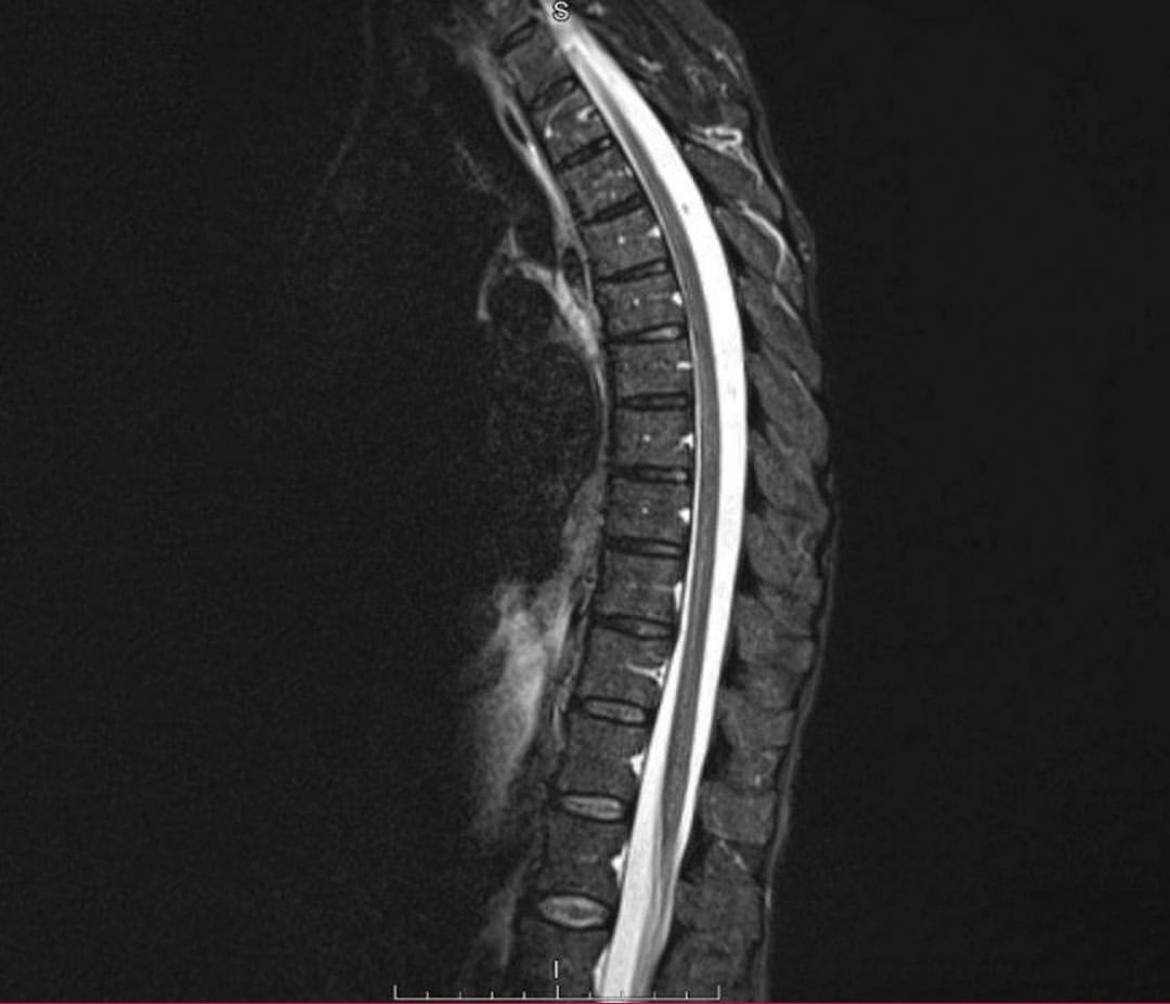

Диагностика показала наличие метастатических процессов с первичным очагом в грудной клетке. Это образование и было причиной болей. Результаты биопсии подтвердили лейомиосаркому.